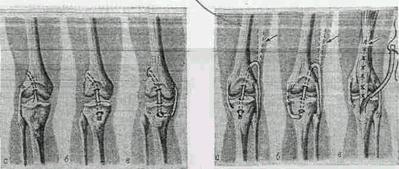

Рис 1.1. Операции на коленном суставе

Рис 1.2. Схема пластики крестообразных и боковых связок